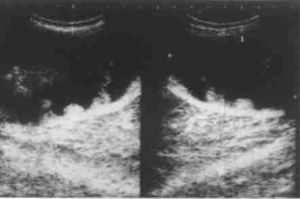

2、B型超聲檢查示子宮增大,宮腔內有液性暗區,內有強光點。

宮腔子宮頸癌在女性生殖系統惡性腫瘤中占首位。由於宮頸易於暴露,可以直接進行細胞學及活體組織檢查,因而超聲一般不作為其首選及必行檢查。而對於宮頸癌合併宮腔內積膿的患者,臨床上多需行超聲檢查以進一步鑑別診斷。

宮頸癌合併宮腔積膿一般沒有特異的臨床表現。超聲表現為子宮體增大,宮腔內充滿液性暗區,暗區內散在疏密程度不等的點狀回聲,積膿較重時肌層受壓變薄。宮頸可表現為正常回聲、不均質回聲或出現異常結節。

超聲對於宮腔積膿的診斷較容易,而要確定是否為宮頸癌所致則較難,在以下情況下應考慮宮頸癌合併宮腔積膿的診斷:(1)老年患者出現宮腔積膿;(2)宮腔積膿而宮體內膜均勻且不增厚;(3)宮腔積膿合併宮頸部回聲異常。

宮頸癌並宮腔積膿應注意與子宮內膜癌合併宮腔積膿鑑別。子宮內膜癌患者多有絕經後陰道出血和陰道排液;聲像圖除宮腔積膿外還表現為子宮內膜瀰漫性不均勻增厚(可達0.6cm以上),或呈團塊狀,子宮肌層常有浸潤,出現不規則異常回聲。患者術前可能被誤診為盆腔囊腫,這是因為子宮體完全失去正常回聲而呈薄壁樣囊性腫塊,此病例提醒我們當老年人發現盆腔內囊性腫塊時應考慮到宮腔積膿的可能性,此時應仔細觀察子宮的情況及與囊性腫塊的關係,以免誤診。